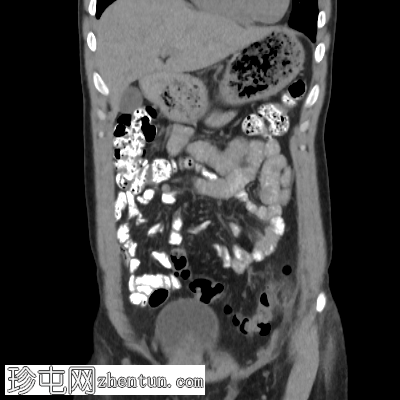

3.jpg

轴位增强扫描(门静脉期)

乙状结肠-降结肠交界处前缘可见一卵圆形脂肪密度病灶,大小约20 x 7 mm(TR x AP)。病灶周围可见高密度环及脂肪条索影,符合大网膜垂炎的影像学表现。

CT扫描显示结肠旁有一小块卵圆形脂肪密度病灶,周围有薄层高密度环(“环状征”),并可见轻度脂肪条索影。未见肠壁增厚、脓肿形成或穿孔,排除了憩室炎等更严重的鉴别诊断。